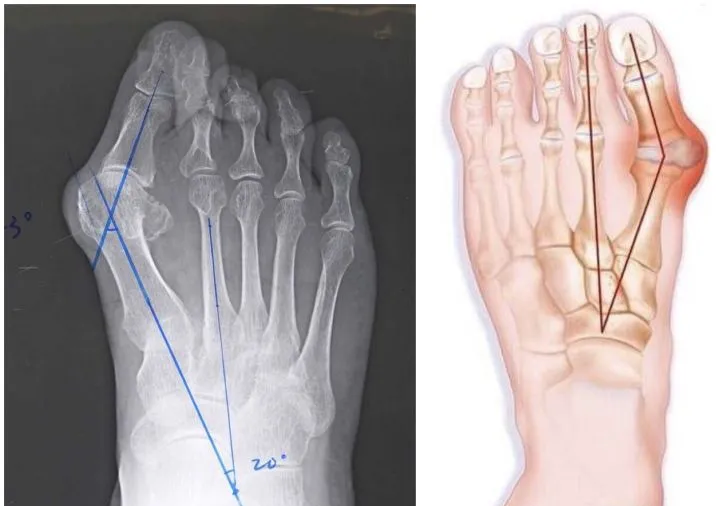

X 线片中可明显看到踇外翻的结构改变